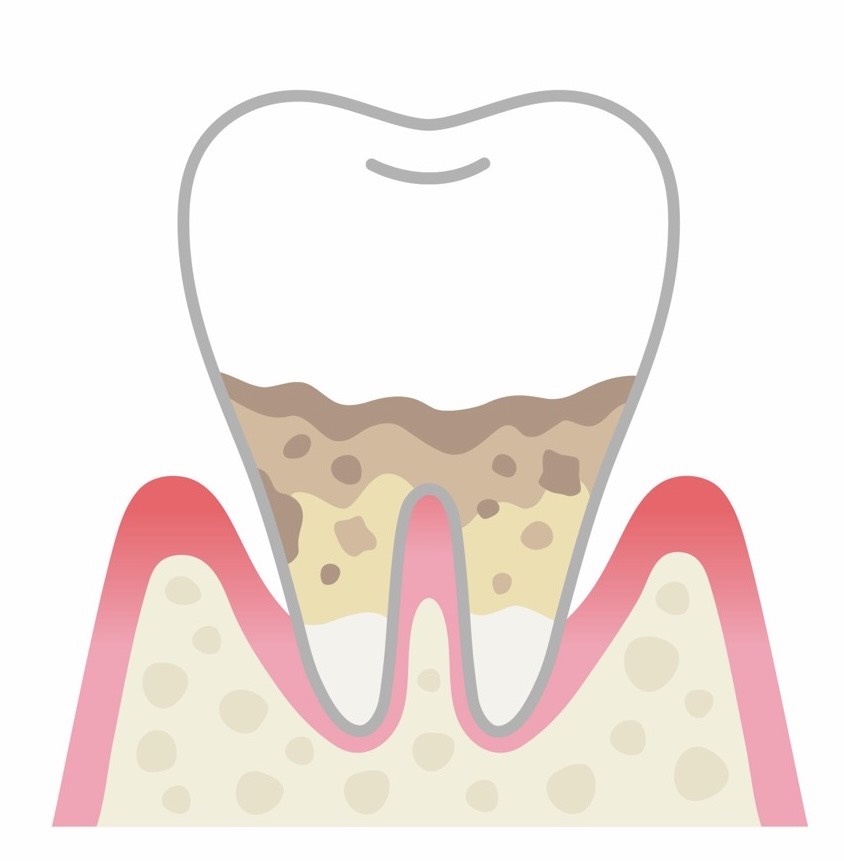

中等度歯周炎

歯周ポケットがさらに深くなり、骨の破壊も進行しています。歯茎が下がって歯が長く見えたり、歯と歯の間に隙間ができたりします。冷たいものがしみる、歯が浮いた感じがする、膿が出るといった症状が現れます。この段階では、歯茎の奥深くに付着した歯石を取り除く必要があり、場合によっては外科的な処置が必要になることもあります。

重度歯周炎

歯を支える骨の大部分が失われ、歯がぐらぐらと動くようになります。歯茎が大きく腫れて膿が出たり、強い口臭が発生したりします。硬いものが噛めなくなり、痛みで食事が困難になることもあります。この段階まで進行すると、抜歯が必要になる可能性が高くなります。